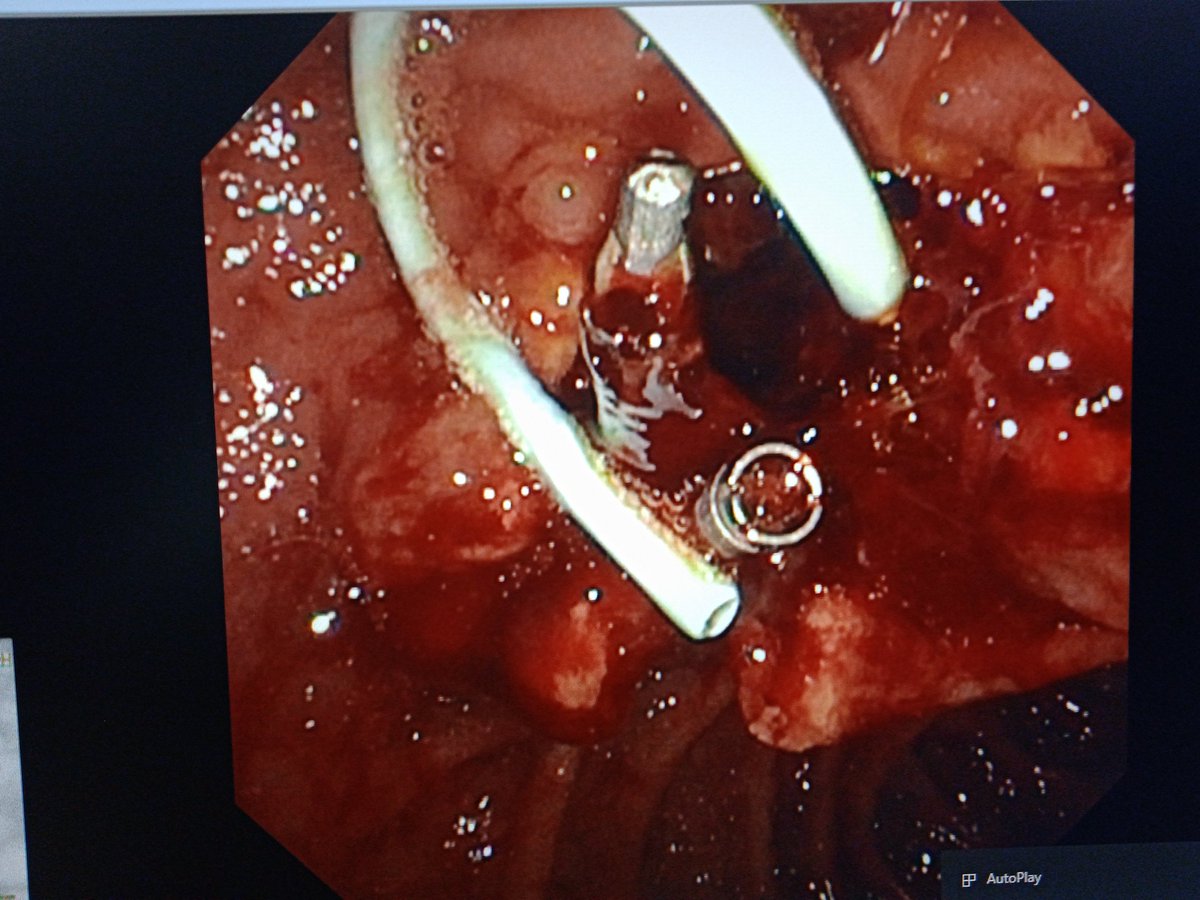

A case of ampullary NET Grade 1 on biopsy Eus/ct/mr suggest lesion limited to ampulla Ampullectomy done. The entire tumor was respected enbloc with intact surrounding capsule There was significant arterial bleeding- controlled with hemoclip application #AIIMSJodhpur